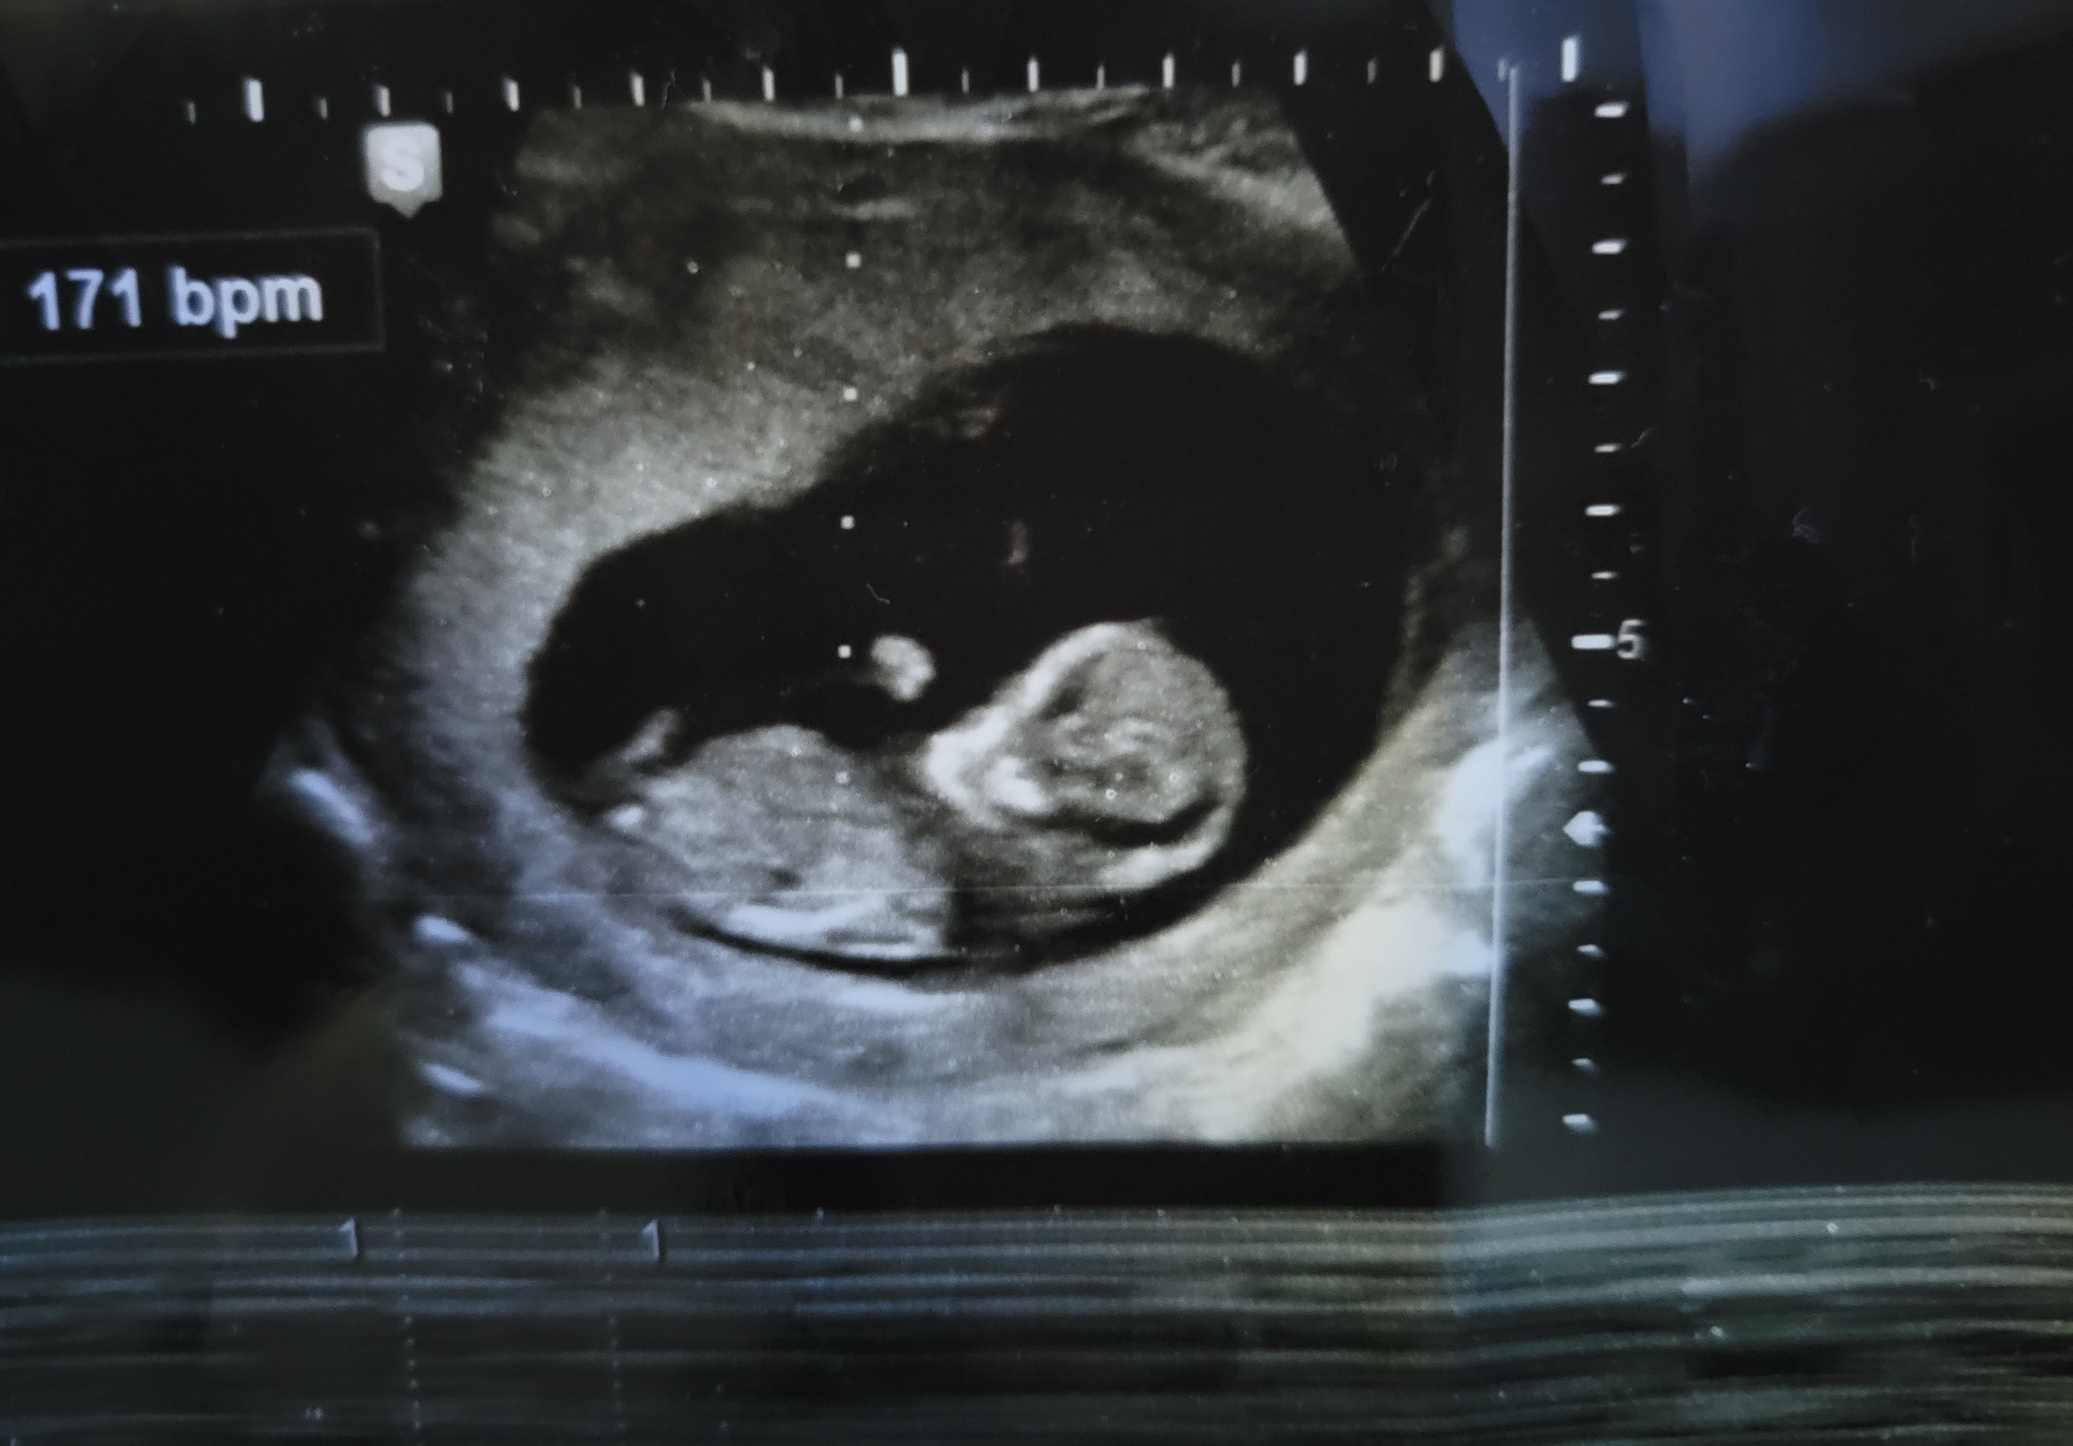

Currently 14 weeks pregnant with my 2nd and I haven't had a single symptom besides missing my period. When I had my first child I was very sick my body told me well before my missed period I was pregnant and I had a girl. Thoughts on if this could be boy?